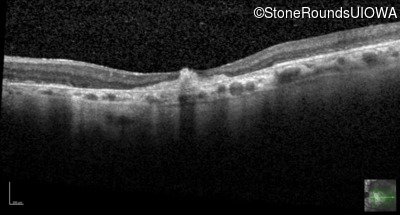

Optical Coherence Tomography - Right - 20/125 -2

Exemplar / OCT Stack

OCT Stack